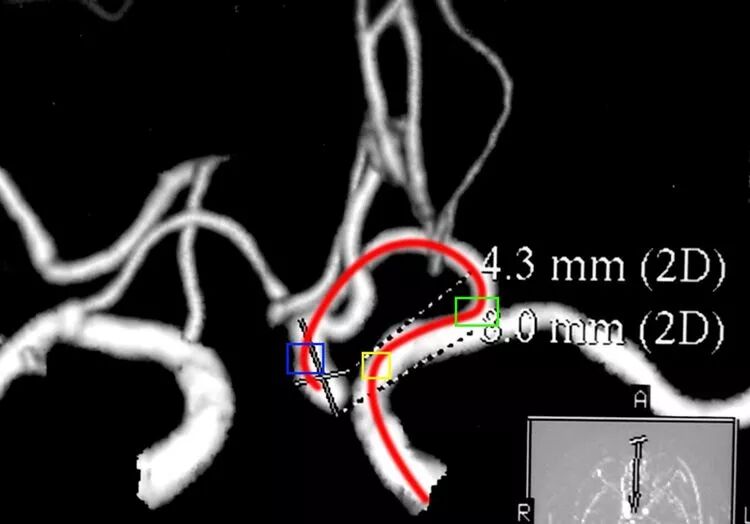

前交通动脉瘤,同理可把微导管头端塑成C形栓塞之,第一个弯儿(蓝方框)便于头端进入瘤腔,第二个弯儿(绿方框)顺应ACA A1段自颈内动脉发出的弧度。更近心端的弯儿(黄方框)不需塑,是微导管顺应动脉路径的自然成形